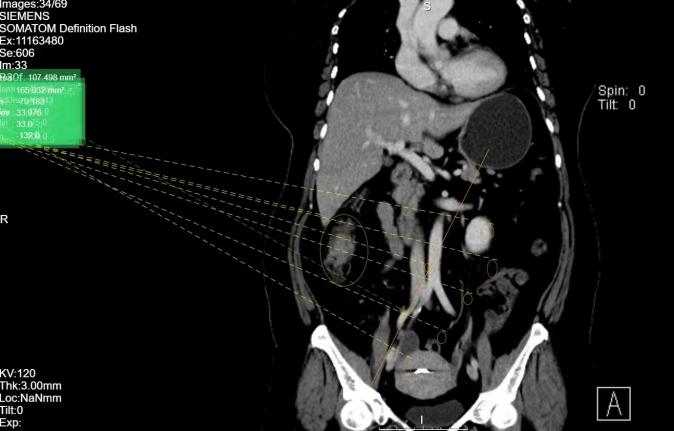

患者杨女士,今年51岁 ,近一周前无明显诱因出现腹胀,无阵发性加剧,伴排便困难,家人赶紧带杨女士来到佛山禅医就诊,门诊肠镜结果考虑杨女士升结肠长了恶性肿瘤。

大外科主任、普外医学部主任区小卫立即组织科室团队进行详细的病情讨论,考虑杨女士体重80KG,BMI36,为了尽量减少术中出血量、减少患者麻醉时间,最终和家属达成一致选择达芬奇手术机器人为患者进行手术,和传统腹腔镜相比,手术机器人直视三维立体高清图像,可以将手术画面放大10-15倍,能更清晰地看到细小的血管和组织,操控更加稳定,安全性更高。